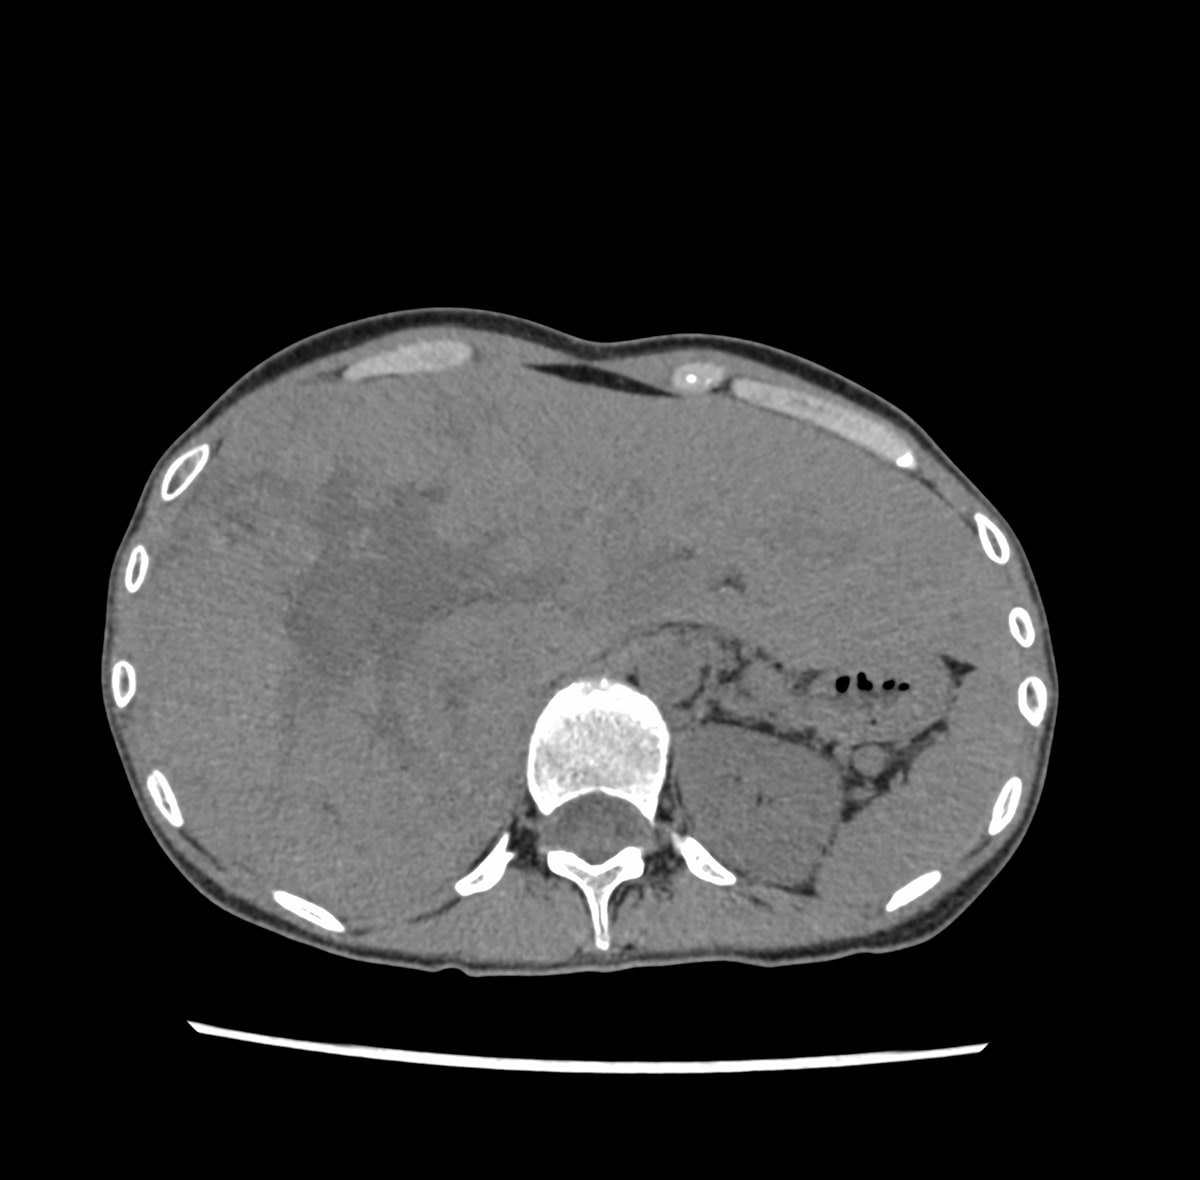

30歳代、女性、38kg、肝細胞癌

右上腹部違和感にて他院を受診し,CTで肝右葉を首座とする巨大肝腫瘍を認め,精査目的に当院紹介.

肝右葉を首座とする24cm大の多結節癒合状の腫瘤性病変を認める.単純CTでは肝実質と等吸収を示し,内部に低吸収域や石灰化を伴っている.造影後早期動脈相から後期動脈相にかけて結節間でやや不均一な早期造影効果を認め,肝静脈相以降では肝実質より相対的に低吸収を示す.門脈本幹から一次分枝レベルにて明らかな造影欠損を認めない.肝細胞癌が疑われ外科的切除が施行され,高~中分化型肝細胞癌と診断された.